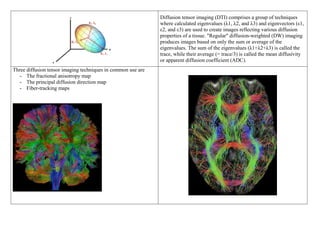

DIFFUSION TENSOR IMAGING

Diffusion tensor imaging (DTI) comprises a group of techniques

where calculated eigenvalues (λ1, λ2, and λ3) and eigenvectors (ε1,

ε2, and ε3) are used to create images reflecting various diffusion

properties of a tissue. "Regular" diffusion-weighted (DW) imaging

produces images based on only the sum or average of the

eigenvalues. The sum of the eigenvalues (λ1+λ2+λ3) is called the

trace, while their average (= trace/3) is called the mean diffusivity

or apparent diffusion coefficient (ADC).

Three diffusion tensor imaging techniques in common use are

- The fractional anisotropy map

- The principal diffusion direction map

- Fiber-tracking maps